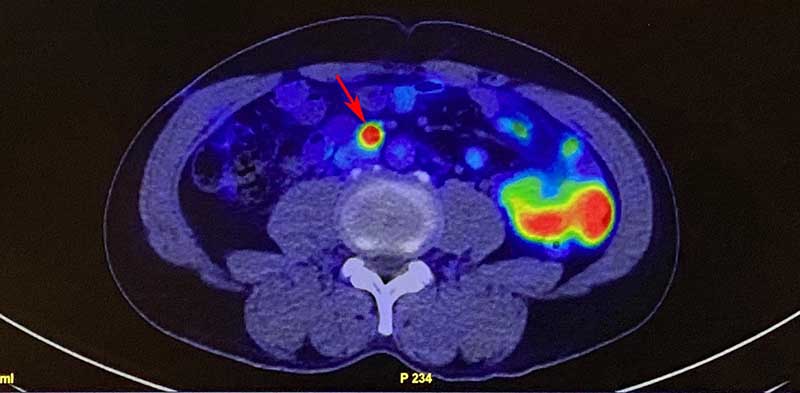

台中63歲高姓男子前年初健檢抽血,發現攝護腺特異抗原指數(Prostate-Specific Antigen,簡稱PSA)異常就醫,確診為攝護腺癌。於臺中榮總接受達文西攝護腺和雙側淋巴切除手術,術後恢復良好,然而後續回診追蹤,PSA指數仍緩慢上升至0.8ng/mL,代表可能有復發或轉移病灶,一般磁振造影無法檢出,高先生焦慮到失眠,回診看報告更是提心吊膽。所幸泌尿醫學部和核子醫學科為他安排最新的PSMA正子斷層掃描檢查,發現下腔靜脈旁有多顆高位淋巴結轉移,給予口服藥和放射線治療後,目前PSA指數正常(< 0.025ng/mL),高先生生活如常也終於放下心中大石。

臺中榮總泌尿醫學部李建儀主任說明,新一代PSMA正子斷層掃描專用於偵測攝護腺癌,適用3種情況:初期診斷時,當病人癌指數很高但傳統影像看不到轉移病灶,新檢查能找出隱藏病灶,精準判定分期;在手術或放射線治療後,若腫瘤指標未明確改善,可重新評估病況及療效;懷疑癌症復發或轉移時,新檢查能在PSA數值0.2至0.5之間就偵測出病灶,讓醫師更早介入治療。林宜瀞主任解釋,PSMA正子斷層掃描顯影劑18F-rhPSMA-7.3於2025年12月獲衛福部核准,影像雜訊更低,能偵測小於5mm的微小病灶。檢查為非侵入性,僅需靜脈注射且無飲食限制,整個流程約1.5至2小時,檢查後可立即回家。目前為自費項目,病人需與醫師討論後做出最適合的治療決策。